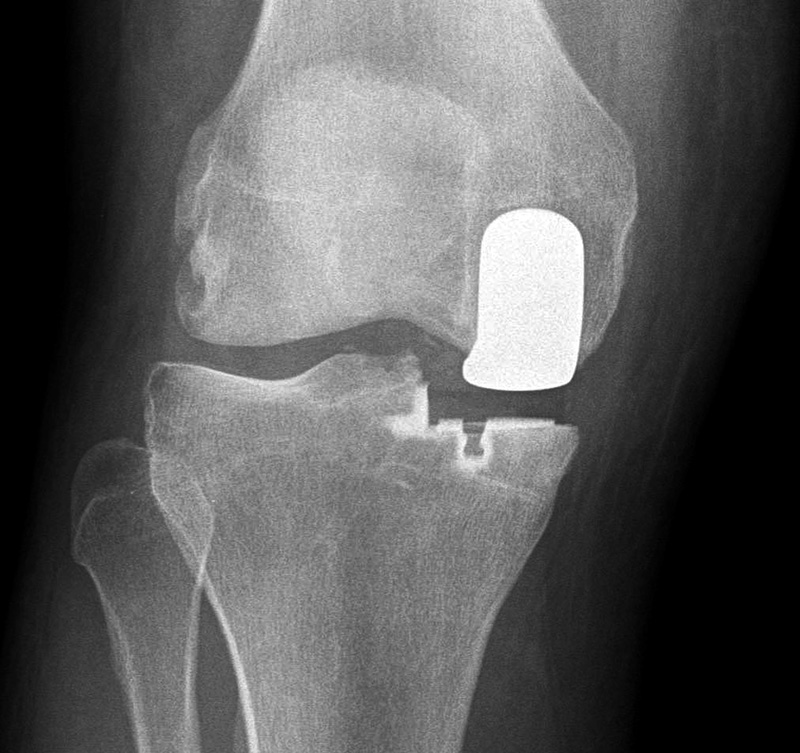

Unicompartmental knee prosthesis placed in the medial compartment (AP view) Unicompartmental knee prosthesis placed in the medial compartment (lateral view) Unicompartmental knee prosthesis placed in lateral knee compartment

Unicompartmental knee prosthesis - AP view Lateral unicompartmental knee prosthesis Lateral unicompartmental knee prosthesis

From Taljanovic, 2005 50 year-old man with lateral knee compartment degenerative osteoarthritis